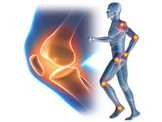

Manuál terápia. Ízületi gyulladás és kezelése. Mágnes terápia

Izom fájdalom kezelése→manuál terápia Mozgás beszűkülés

javítása. A terápia teljesen biztonságos, fájdalmatlan és gyorsan hat. Az ízületi

gyulladás okozta fájdalmat a Motion Energy gél jelentősen csökkenti. Étrenddel

az ízületi gyulladás ellen. Omega-3 zsírsavak gyulladáscsökkentő

hatásuknak köszönhetően csillapítják az ízületi fájdalmakat. A lágylézer

terápiában alacsony energiájú, infravörös lézersugárral történik a kezelés. A

lökéshullám-terápia fókuszált, nagy intenzitású hanghullámmal történik. Az ultrahang

kezelés az alábbi betegségekre különösen alkalmas: -Ízületi betegségek, -

Lumbágó, - Csípő betegségek. Orvostechnikai eszköz: CE0483, a BEMER

készülék (foto) bérelhető. Mágnes terápia hatása –Csontrendszer, -Izomrendszer,

-Légzőszervi rendszer, -Ideg rendszer, -Keringési rendszer